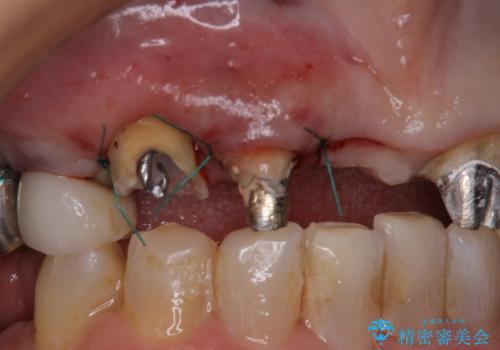

ところが、土台となる歯は、十分な維持力が得られないほど歯ぐきの中に埋もれており、歯ぐきも腫れやすい状況でした。

まずは土台の歯を引っぱり出し、外科処置により歯肉の状態を十分に整えた上で、オールセラミッククラウンにて補綴することとしました。

元々の土台は歯肉の中に埋もれており、歯肉が著しく腫れている状態だったため、歯を引っぱり出すこととしました。引っぱる期間は2ヶ月ほどで済み、その後歯周外科処置を行ったことで、土台周りの歯肉は腫脹のない健全な状態へと改善されました。